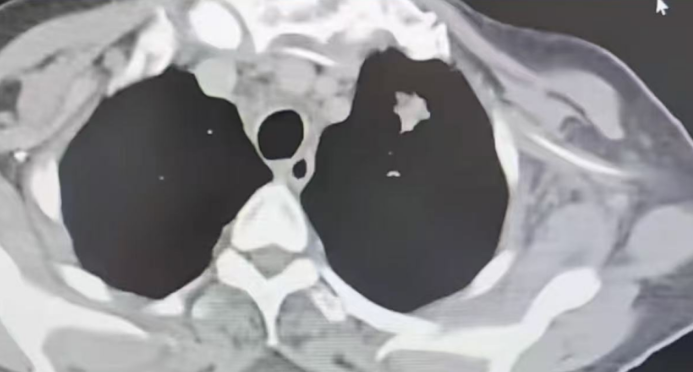

近日,济南南郊医院肿瘤一科对一名老年女性肺部肿瘤患者进行了针对性治疗。该患者入院时病情危重,长期卧床不起,伴有呼吸困难、全身乏力、胸闷憋喘及头痛等症状,生活无法自理。经肿瘤一科葛新华主任详细检查,确诊为左肺门占位性病变,伴有纵隔淋巴结肿大、双肺慢性阻塞性炎症,且肿瘤已发生颅脑转移,病情复杂危重。

令人欣慰的是,经过两次规范治疗,患者症状明显改善:由卧床不起转为可下地自由活动,胸闷、咳嗽等症状基本消失,生活恢复自理能力,并可从事适当家务。影像学复查显示,患者双肺结节显著减少,纵隔淋巴结明显缩小,右肺门肿块也较前减小,疗效评估达到完全缓解(CR)的临床标准。